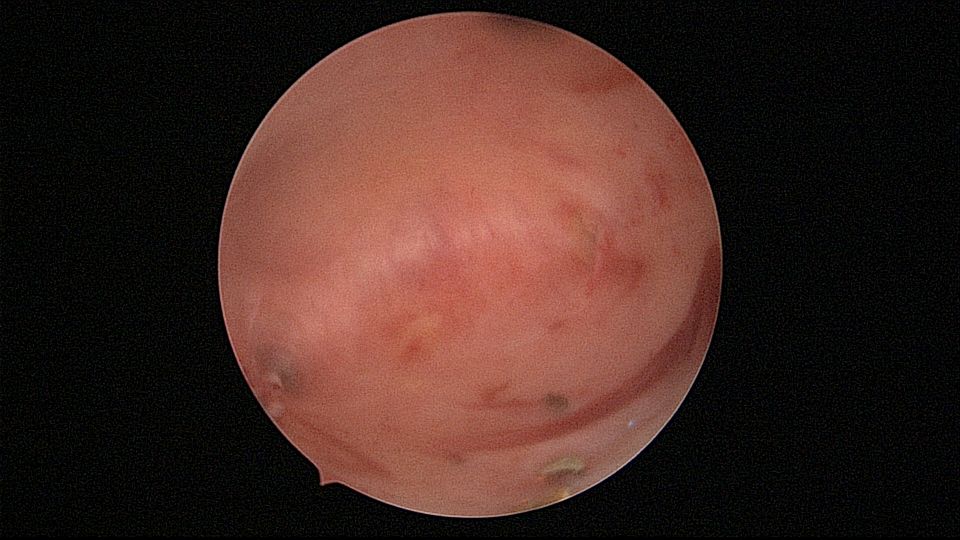

患者53岁,G3P1,剖宫产1次。安环13年,绝经8年,外院取环失败。患者阴道、宫颈及子宫萎缩,很难置入扩阴器,很难牵拉宫颈,宫颈外口位于前穹隆顶端,子宫极度前倾前屈位,且子宫与盆壁粘连,被拉长,宫腔镜很难进入,B超监护下异物钳扩张宫颈管上段及宫颈内口,宫腔镜艰难进入宫腔,见T型环两横臂嵌顿于两侧宫角,尾丝断裂,异物钳取出节育环,宫腔未见其他异常。